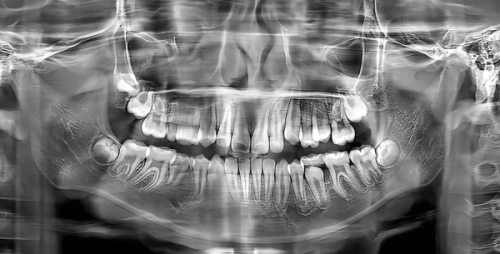

儿童口腔科主要针对0-14岁孩子的牙齿问题,与牙科相比更注重预防和早期干预。以下是常见的儿童口腔治疗项目及参考价格:

儿童早期矫正:8000-20000元起。针对牙齿排列不齐、咬合异常等问题,佳干预年龄为7-9岁。